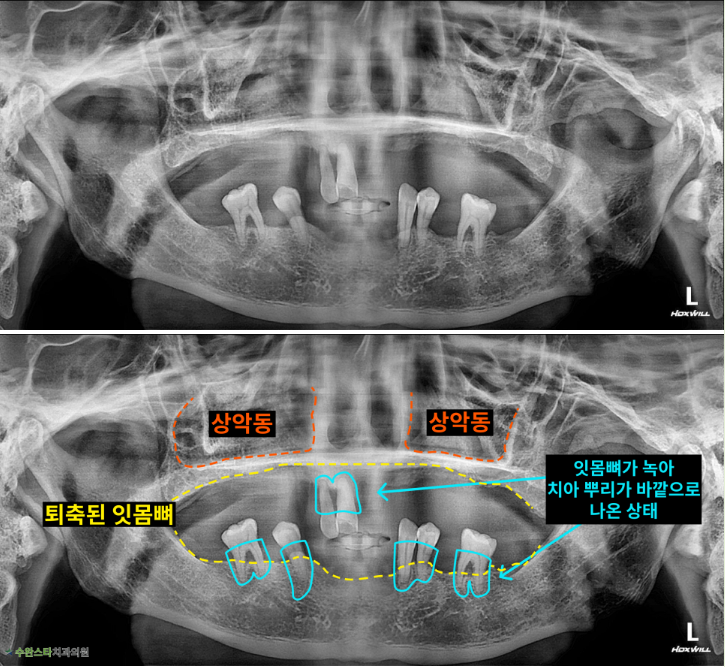

내원 시 파노라마

처음 내원 시 파노라마, 50대 남성 (2025.7 촬영)

내원 시 파노라마 사진입니다.

잇몸뼈가 위 아래 모두

많이 퇴축된 모습이라

자연치아를 살릴 수 없어

발치 후 뼈 이식과 임플란트가

필요합니다.

이처럼 잇몸뼈가 부족한 경우에는

상악동 거상술을 통한

전체적으로 뼈이식이 필요합니다.